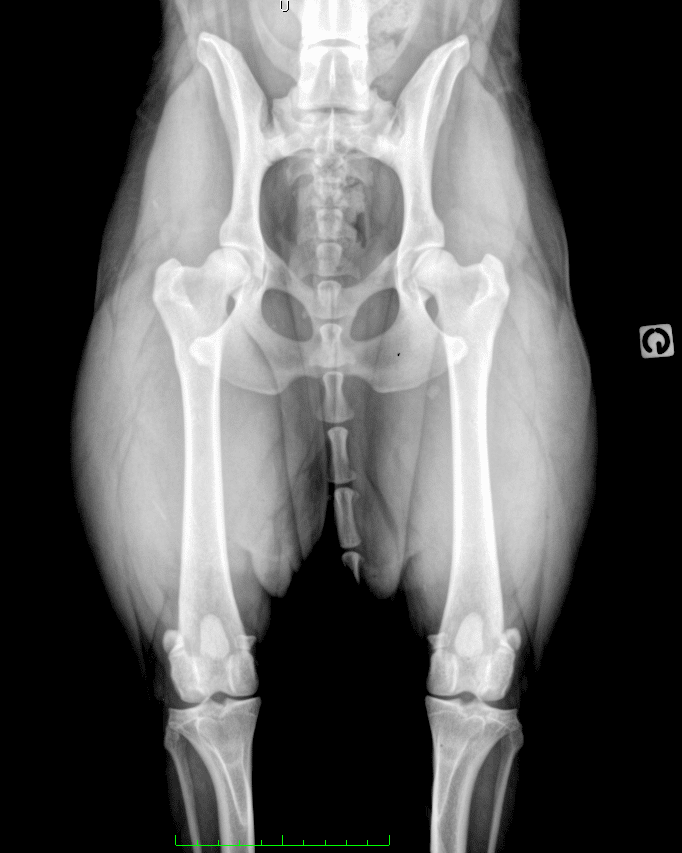

Dysplasie de la hanche chez le chien